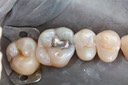

Larry Fujioka #20-21 pre-op

Larry Fujioka #20-21 caries removal